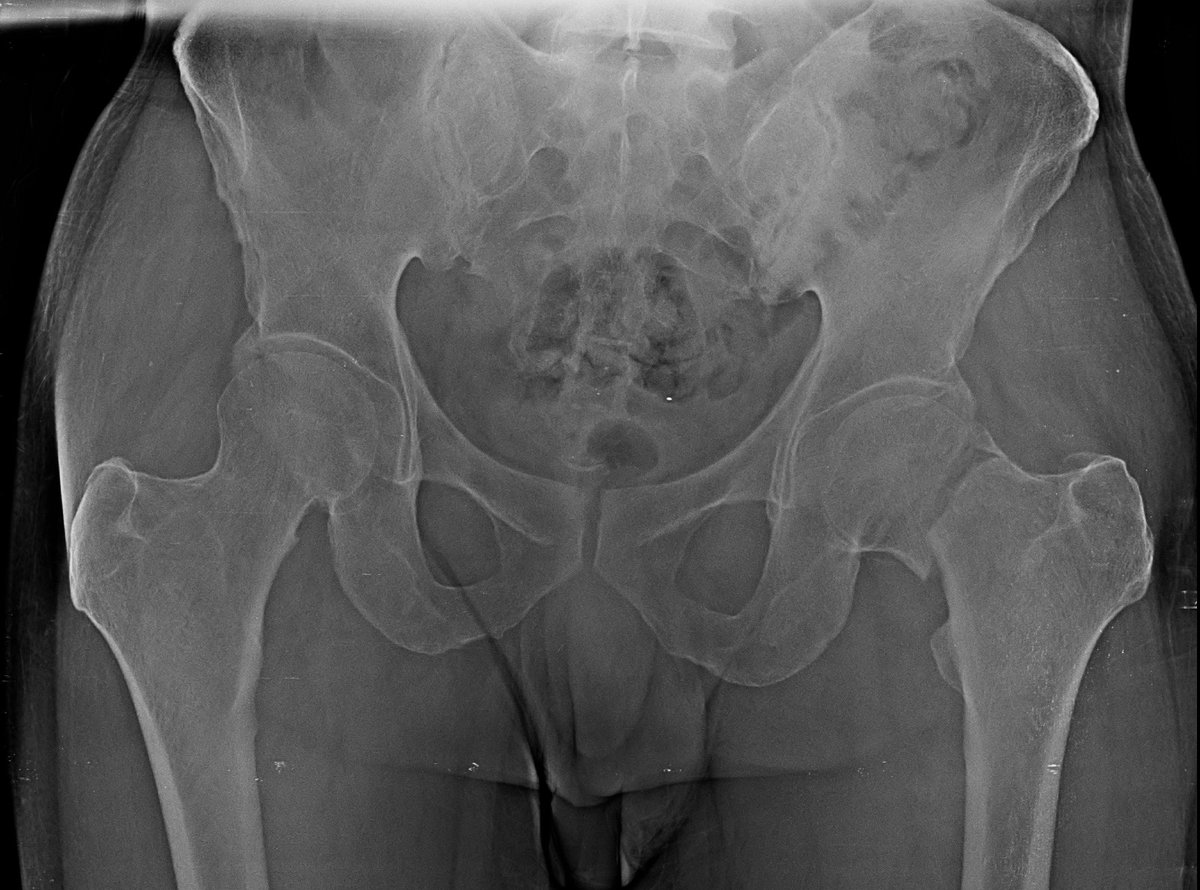

Neck of femur fracture in 55 year old gentleman,

Pauwel type 2

Mild Comminuted !

Did DHS with CC Screw.

#medtwitter #medx #orthotwitter #orthox #fracture